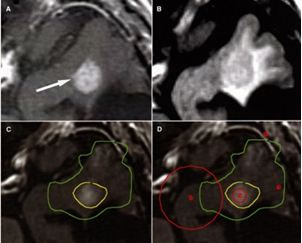

Hình 23: Hình ảnh mô tả kế hoạch bên trong kế hoạch. Hình (A) Chụp cộng hưởng từ bệnh nhân có glioblastoma cho thấy khối u tăng ở thùy thái dương bên trái (mũi tên). Hình (B) hình ảnh này có ý nghĩa quan trọng biểu hiện tổ chức quanh u trên xung FLAIR. Hình (C) xây dựng kế hoạch xạ phẫu gamma vùng xung quanh ngấm thuốc khối u với đường đồng liều 50% (màu vàng), trên xung FLAIR là 38% (màu xanh). Hình (D) Tương tự như kế hoạch C chỉ ra vị trí xuất hiện của 2 shot.

Đường đồng liều 50% được xây dựng với tỷ trọng cao, shot nhỏ, trong khi đường đồng liều 38% có cấu trúc tỷ trọng thấp, shot lớn.

Bệnh nhân Đinh Thị Th.; nữ, 42 tuổi. Chẩn đoán: glioblastoma thùy thái dương. Chỉ định: xạ phẫu dao gamma quay (RGK) liều 20Gy”